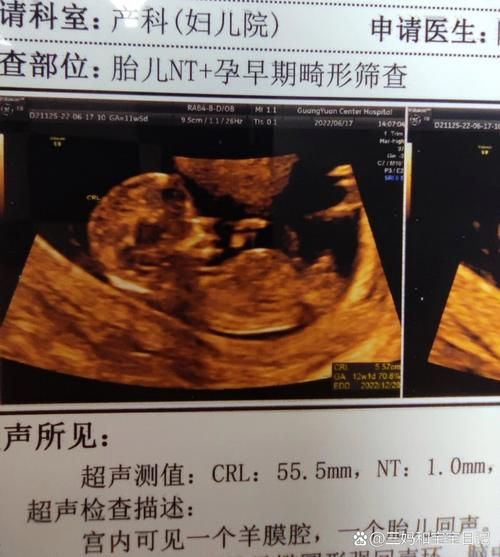

拿到四维报告,看到“胎儿鼻骨缺失”五个字,多数准爸妈瞬间大脑空白。它并不等于孩子一定畸形,而是提示染色体异常风险升高,**最常见关联的是21三体(唐氏综合征)**。 医生通常会建议无创DNA或羊水穿刺进一步排查,**影像上没拍到鼻骨,也可能只是体位遮挡或骨化延迟**。

来自广州的林女士在22周大排畸被告知“双侧鼻骨未显示”,夫妇俩彻夜难眠。经过羊水穿刺+基因芯片,结果提示胎儿染色体正常。抱着忐忑,她坚持妊娠,39周顺产一名3.2 kg女婴,**出生后鼻梁略低但呼吸通畅,6个月随访时鼻骨已可见骨化**。 她把孕期B超照片与出生照对比,发现**宫内软组织塌陷让鼻梁“隐形”,生后脂肪垫增厚,轮廓自然显现**。

- 第一步:确认孕周——鼻骨在11周开始骨化,14周前未显示属正常。